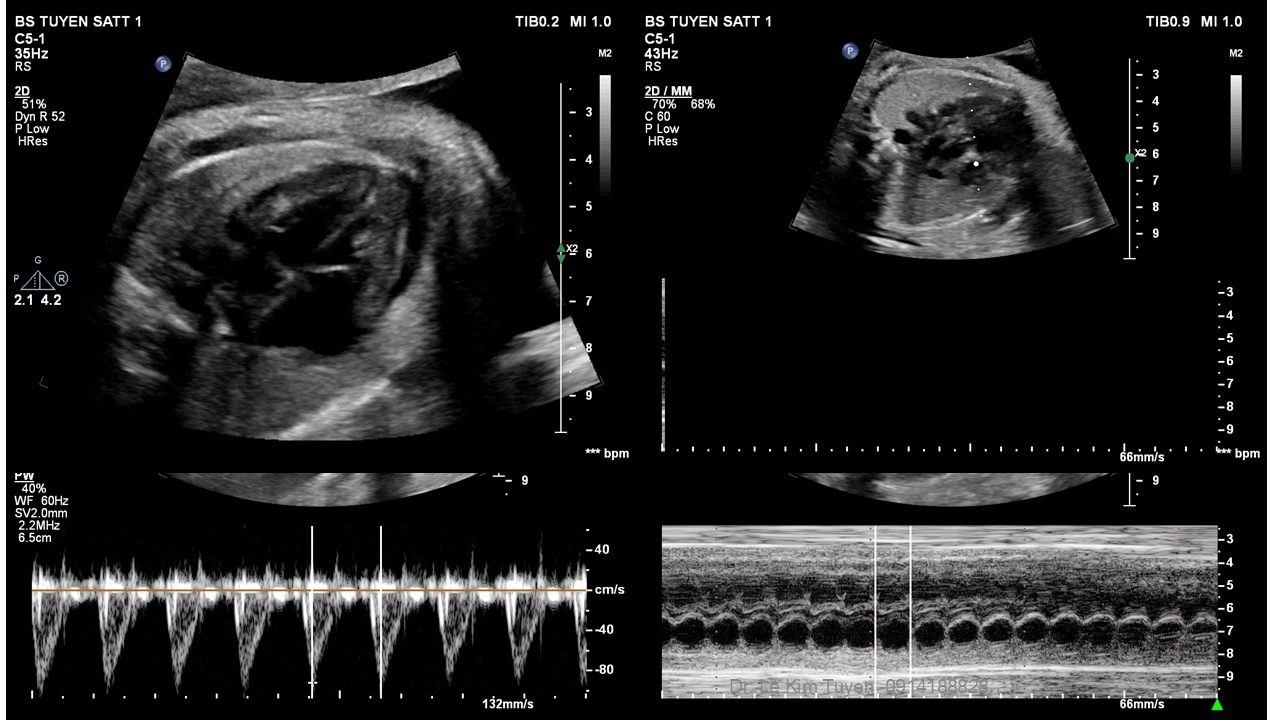

Áp dụng công nghệ Graphicflow trong phát hiện bệnh tim bẩm sinh cần cấp cứu sơ sinh

TS. BS. Lê Kim Tuyến

Bệnh viện Tim Tâm Đức